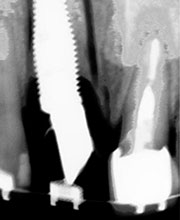

Paciente femenino a la cual le colocaron implante alto verticalmente, presentando a la vista una corona con un excedente de aproximadamente 5 milímetros, de porcelana rosa.

La paciente inconforme con los resultados nos visita, realizamos estudios radiográficos y tomográficos, encontrando que se perdió hueso verticalmente en el implante.

Radiografía del poste de guía